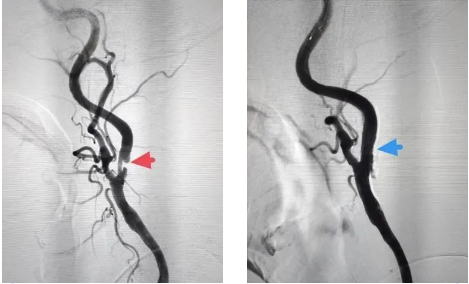

赵爷爷是因为突然出现右侧肢体无力入院的,既往高血压、高脂血症。入院后确诊为左侧Knob区脑梗死,完善血管检查发现左侧颈内狭窄。仔细的术前评估、术前讨论后行血管造影术,术中发现右侧颈内动脉重度狭窄(左图-红箭头),与家属充分沟通后同意同期行左侧颈动脉球囊扩张及支架置入术,术后支架位置良好,贴壁佳,血流通畅(右图-蓝箭头),妥善解决了其血管狭窄问题。术中及术后患者无不适,赵爷爷治疗后症状明显好转出院。